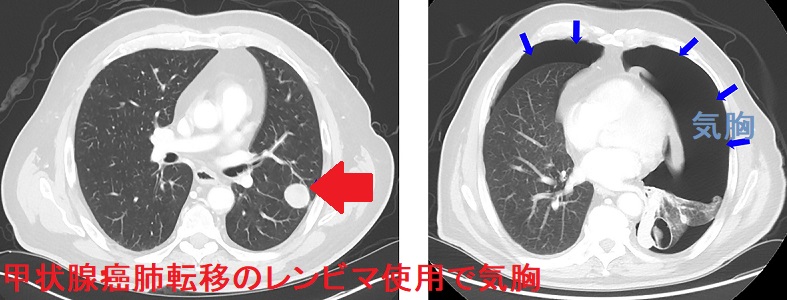

肺の表面近くにできた甲状腺癌の肺転移巣が壊れ(壊死)、肺を包む臓側胸膜が破れると、肺内の空気が漏れだします(気胸)。

甲状腺癌の肺転移巣が壊れて(壊死)、気胸を形成する原因は、

- 甲状腺癌細胞が増殖し過ぎて血流の悪くなった部分が壊死する;甲状腺癌の自然崩壊(自壊)

- 根治切除不能な甲状腺癌に対する治療薬 レンビマ®(レンバチニブ)の効果で甲状腺癌が壊死する

休薬のみで気胸は治癒し、再投与で再発する(第62回 日本甲状腺学会 P14-5 気胸のためレンバチニブからソラフェニブに変更した乳頭癌肺転 移の1例)

脱気や胸膜癒着術を行う場合もある(Case Rep Endocrinol. 2018 Mar 28;2018:7875929.)

などです。(Respir Med Case Rep. 2019 Jan 8;26:197-199.)